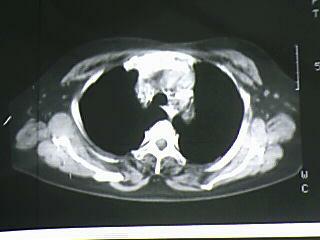

以下是引用bmw011在2009-4-14 19:14:00的发言:[br]右肺继发型肺结核---纵隔淋巴结多发钙化----左肺支扩。支持

以下是引用杀毒软件在2009-4-14 17:52:00的发言:[br]考虑---右肺继发型肺结核---纵隔淋巴结多发钙化----左肺支扩

以下是引用黑白光影在2009-4-14 20:36:00的发言:[br]右肺继发型肺结核;左下慢性支气管炎性病变。